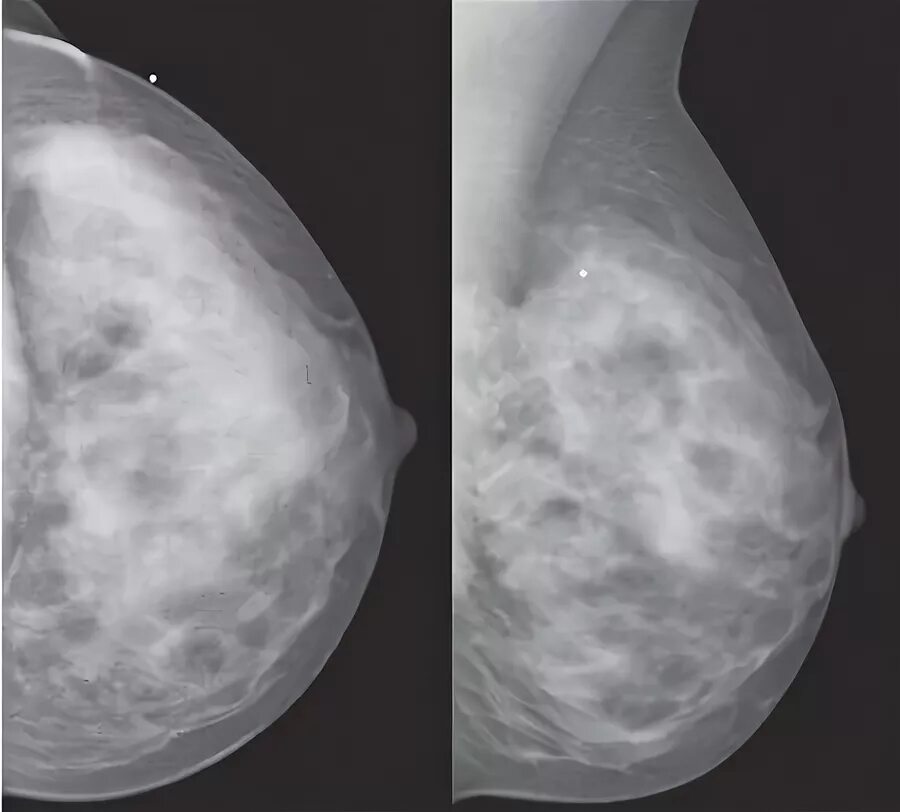

Доброкачественное новообразование молочной железы